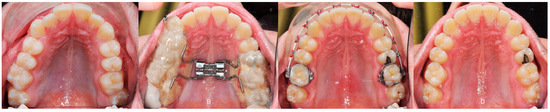

3. The Results of the Treatment